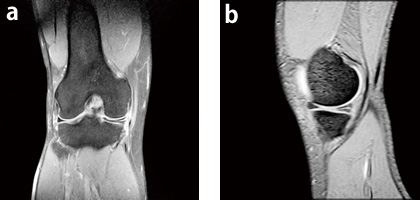

症例2:右内側半月板損傷右膝疼痛と軽度の関節腫脹があり,MRIを撮像。

右内側半月板後角損傷と関節液貯留を認める。

a:PDWI,COR,fatsat,TR/TE:1800/12,FA:90°,スライス厚:3mm

b:T2*WI,SAG,FOV:150mm,TR/TE:3600/80,FA:90°,スライス厚:3mm